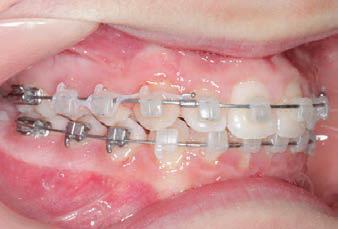

CLASS II DIV.1 - Marra

INITIAL - 4/4/18

PROGRESS 1 - 26/9/18 - Class I platform accomplished in 5.75 months with Motion 3D COLOR Appliance

PROGRESS 2 - 26/9/18 - Placement of the SLX 3D Clear Brackets

with M-ONE .015 Cu Nitanium 27°

PROVIDED BY: DR. LUIS

PROGRESS 3 - 30/10/18 - With M-TWO .020 x .020 Cu Nitanium 35° archwire

PROGRESS 4 - 27/11/18 - 3 links power chain: 5, 4, bypass 3 to crimp hooks

PROGRESS 5 - 13/3/19 - With M-TWO .020 x .020 Cu Nitanium 35° archwire

PROGRESS 6 - 1/8/19 - With M-THREE.019 x .025 Beta Titanium wire

FINAL - 10/10/19 - Appliances removed AFTER

PROGRESS 7 - 10/10/19 - Final day in SLX 3D Clear Brackets BEFORE